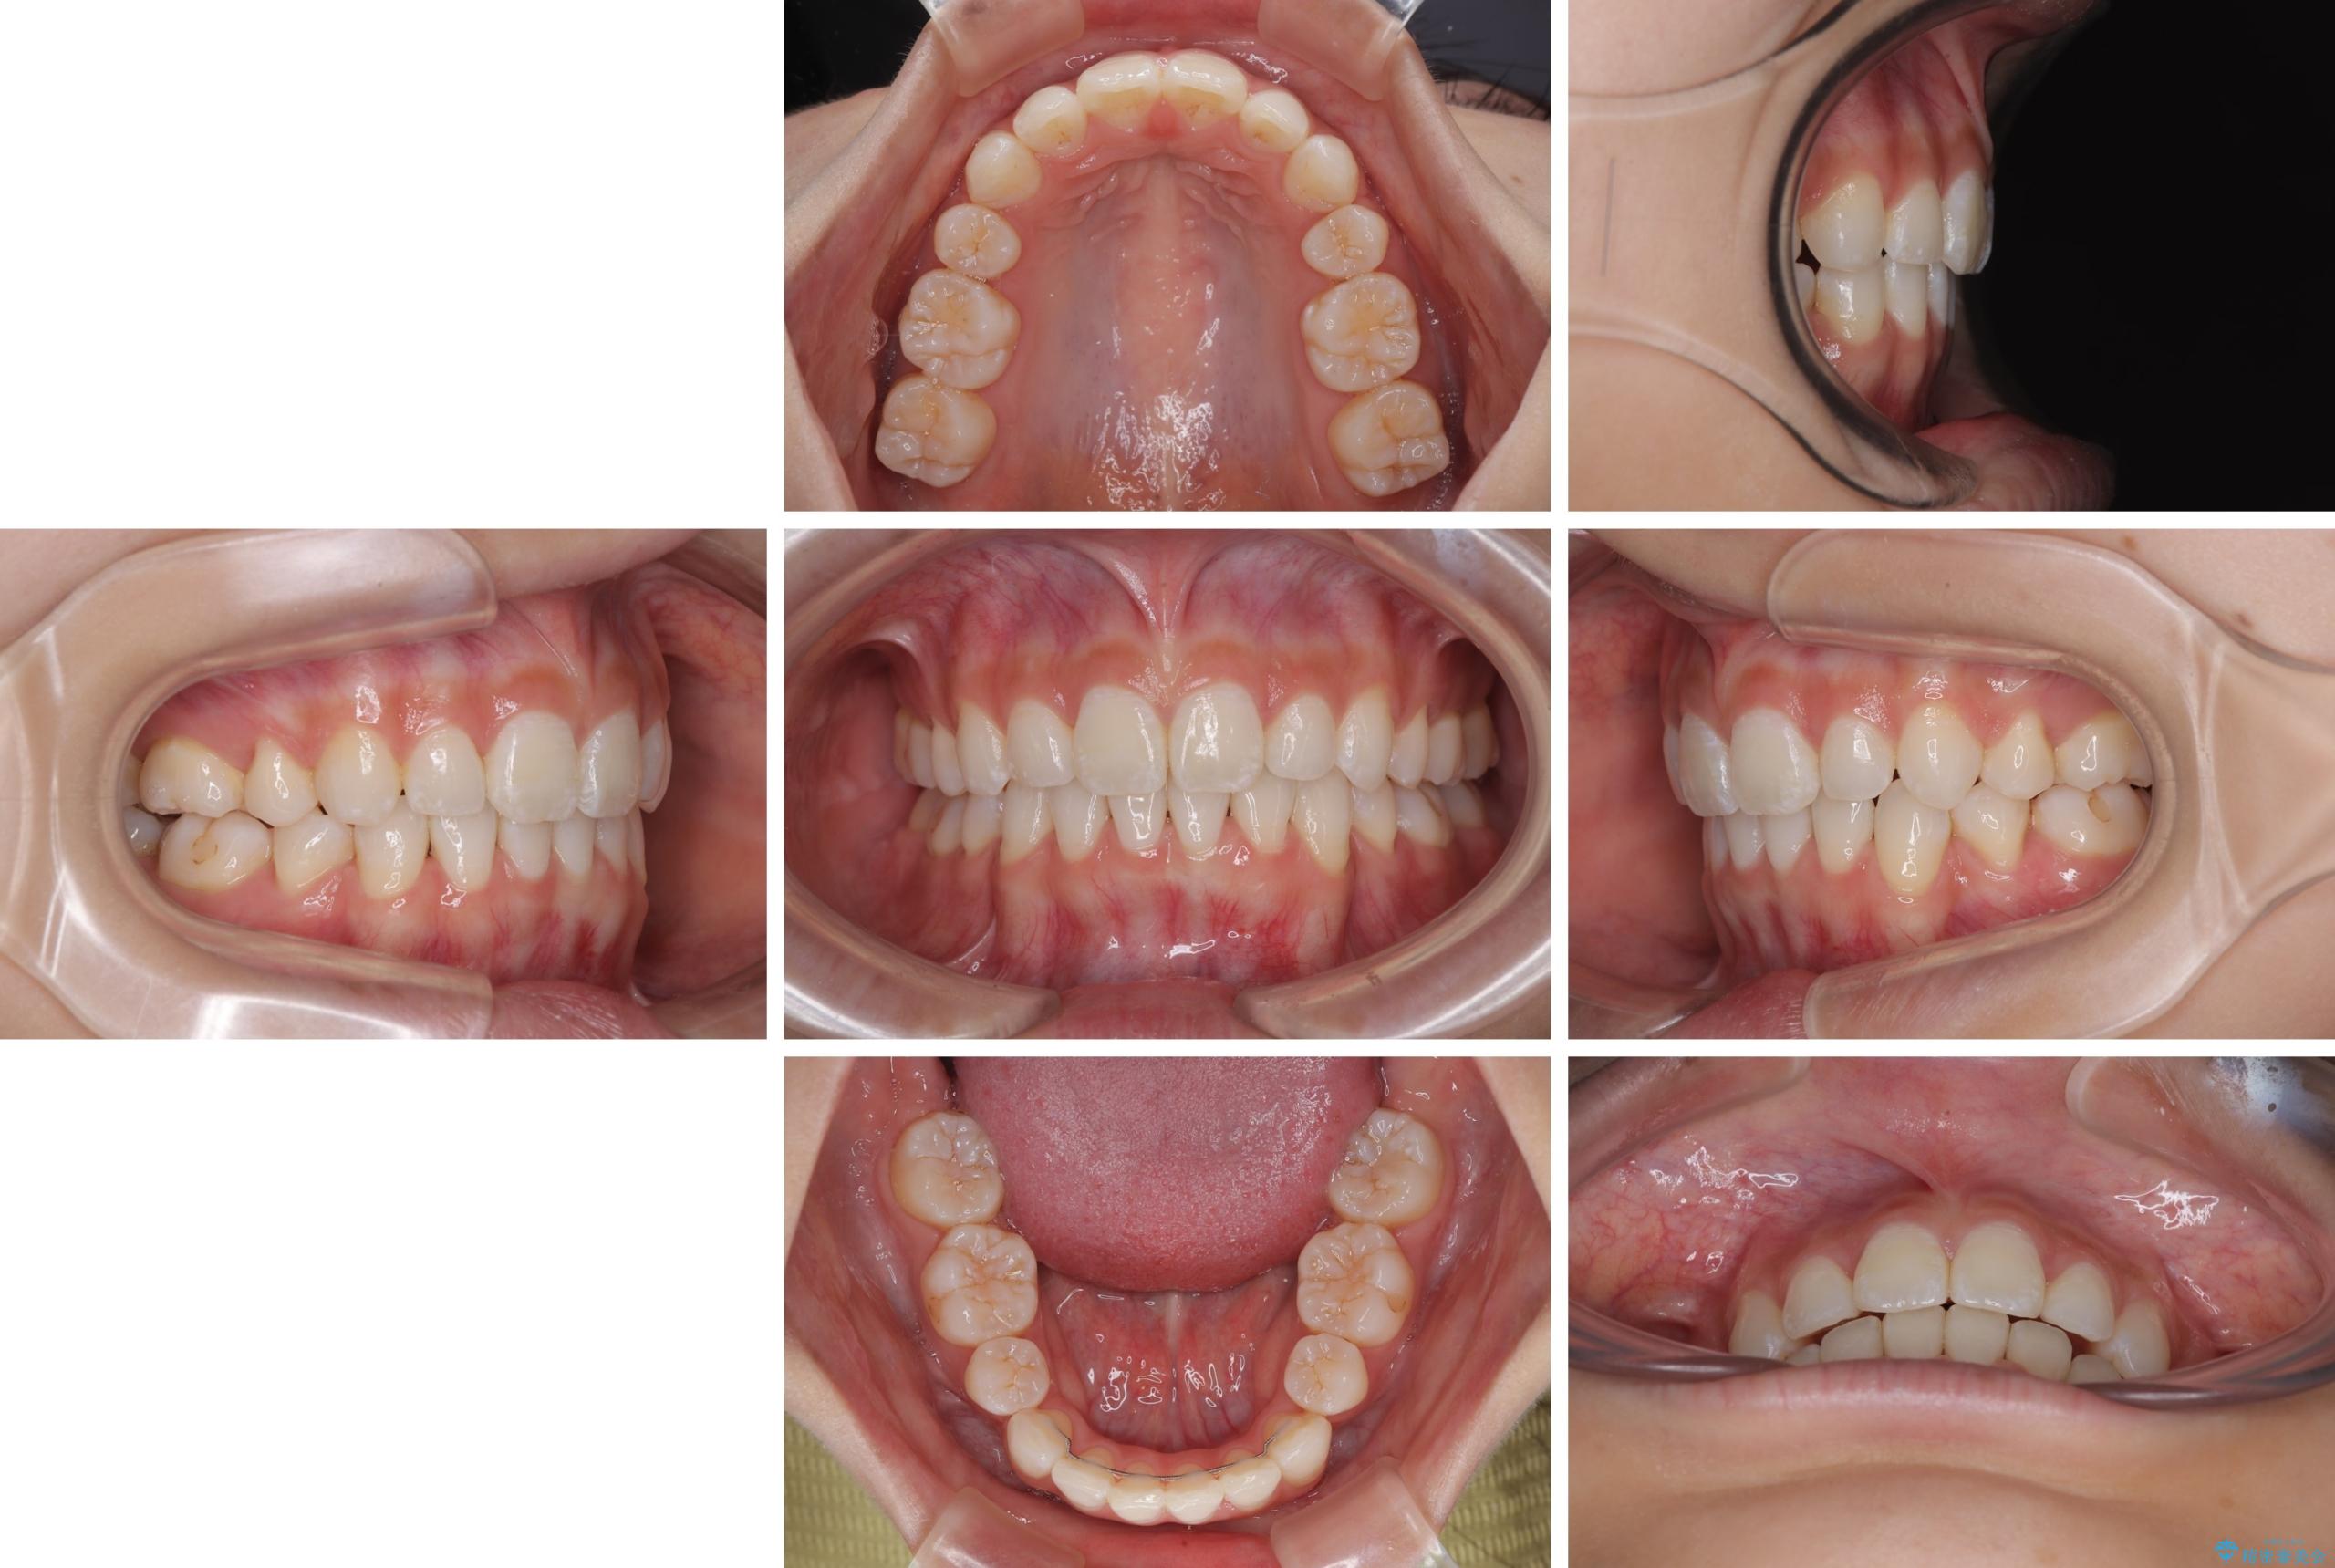

下唇に前歯が当たって跡が残ってしまう状態でしたが、スッキリとした口元に仕上げることができました。

- 口を閉じたときに飛び出してしまう上顎前歯を気にして来院された患者様です。

下顎はデコボコが気になっていたため、上下左右第一小臼歯4本を抜去して、ワイヤー装置にて口元の突出感を改善するよう矯正治療を行うこととしました。